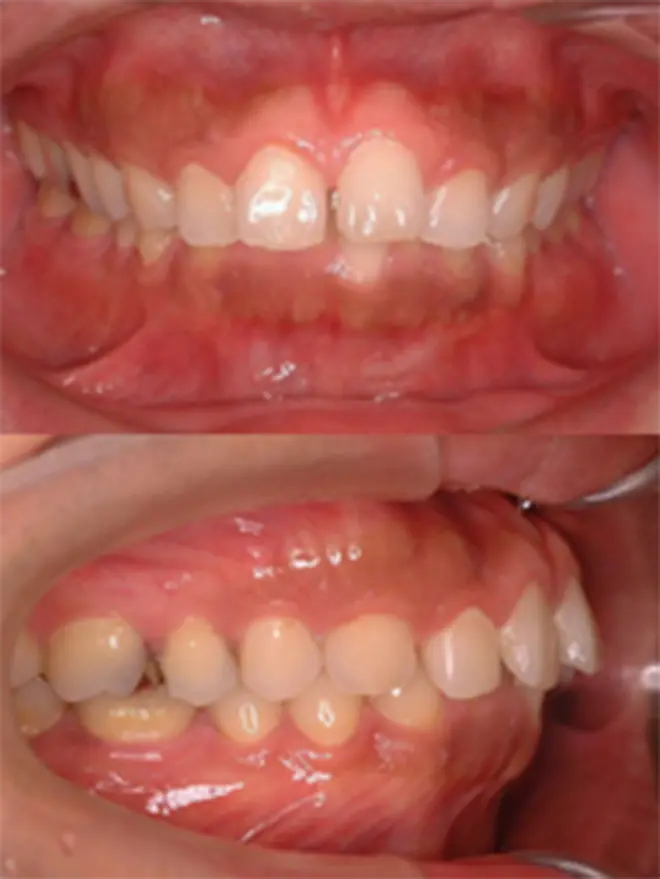

| 患者さまの年齢・性別 | 20代・男性 |

|---|---|

| 治療期間 | 2年 |

| 治療費(税込) | 1,056,000円 |

| 主訴 | 前歯で噛めない。 |

| 診断名・主な症状 | 開咬をともなう下顎前突 |

| 治療に用いた主な装置 | セルフライゲーションブラケット装置(デイモンシステム)、歯科矯正用アンカースクリュー |

| 治療内容 | 下顎の左右奥に1本ずつ歯科矯正用アンカースクリューを埋入し、その力で下顎歯列の後方移動と前歯の噛み合わせの調整を行ないました。 |

| 抜歯部位 | 非抜歯 |